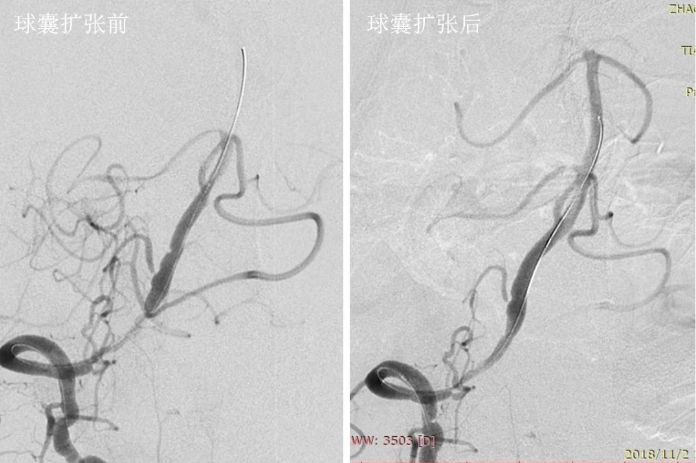

全麻下右股动脉入路, 将6F导引导管放至右椎动脉V2段远端,造影示右椎动脉V4段重度狭窄,狭窄率约为95%,狭窄长度13mm(图8)。

图8

路径图下沿导引导管送入Transend微导丝(0.014″,300cm)越过病变至基底动脉中段,沿微导丝送入Gateway球囊(2.75mm×15mm)于狭窄处预扩张(图9)。

图9